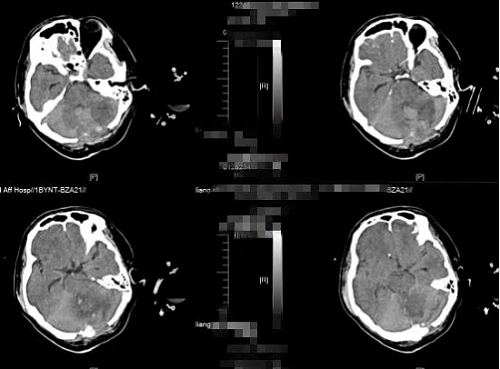

急诊科当即为患者开辟绿色通道,以全力赴抢救患者为先,及时为桂先生进行心肺复苏、气管插管、呼吸机辅助呼吸。神经外科二区伍贞宇医生在接到急诊科通知后,第一时间赶到急诊科评估病情,同时汇报神经外科二区科主任王鹏主任。该患者当时已处于深度昏迷状态,双侧瞳孔直径约2mm,对光反应消失,无自主呼吸及心跳。在协同急诊科抢救后患者心跳恢复,但仍无自主呼吸,病情仍十分危重,急诊行CT提示“左侧小脑半球脑出血并破入脑室,第四脑室及脑干受压,继发幕上脑室轻度脑积水,环池消失。”,脑内出血较前明显增多,脑疝形成,需立即进行手术。

图1术前CT